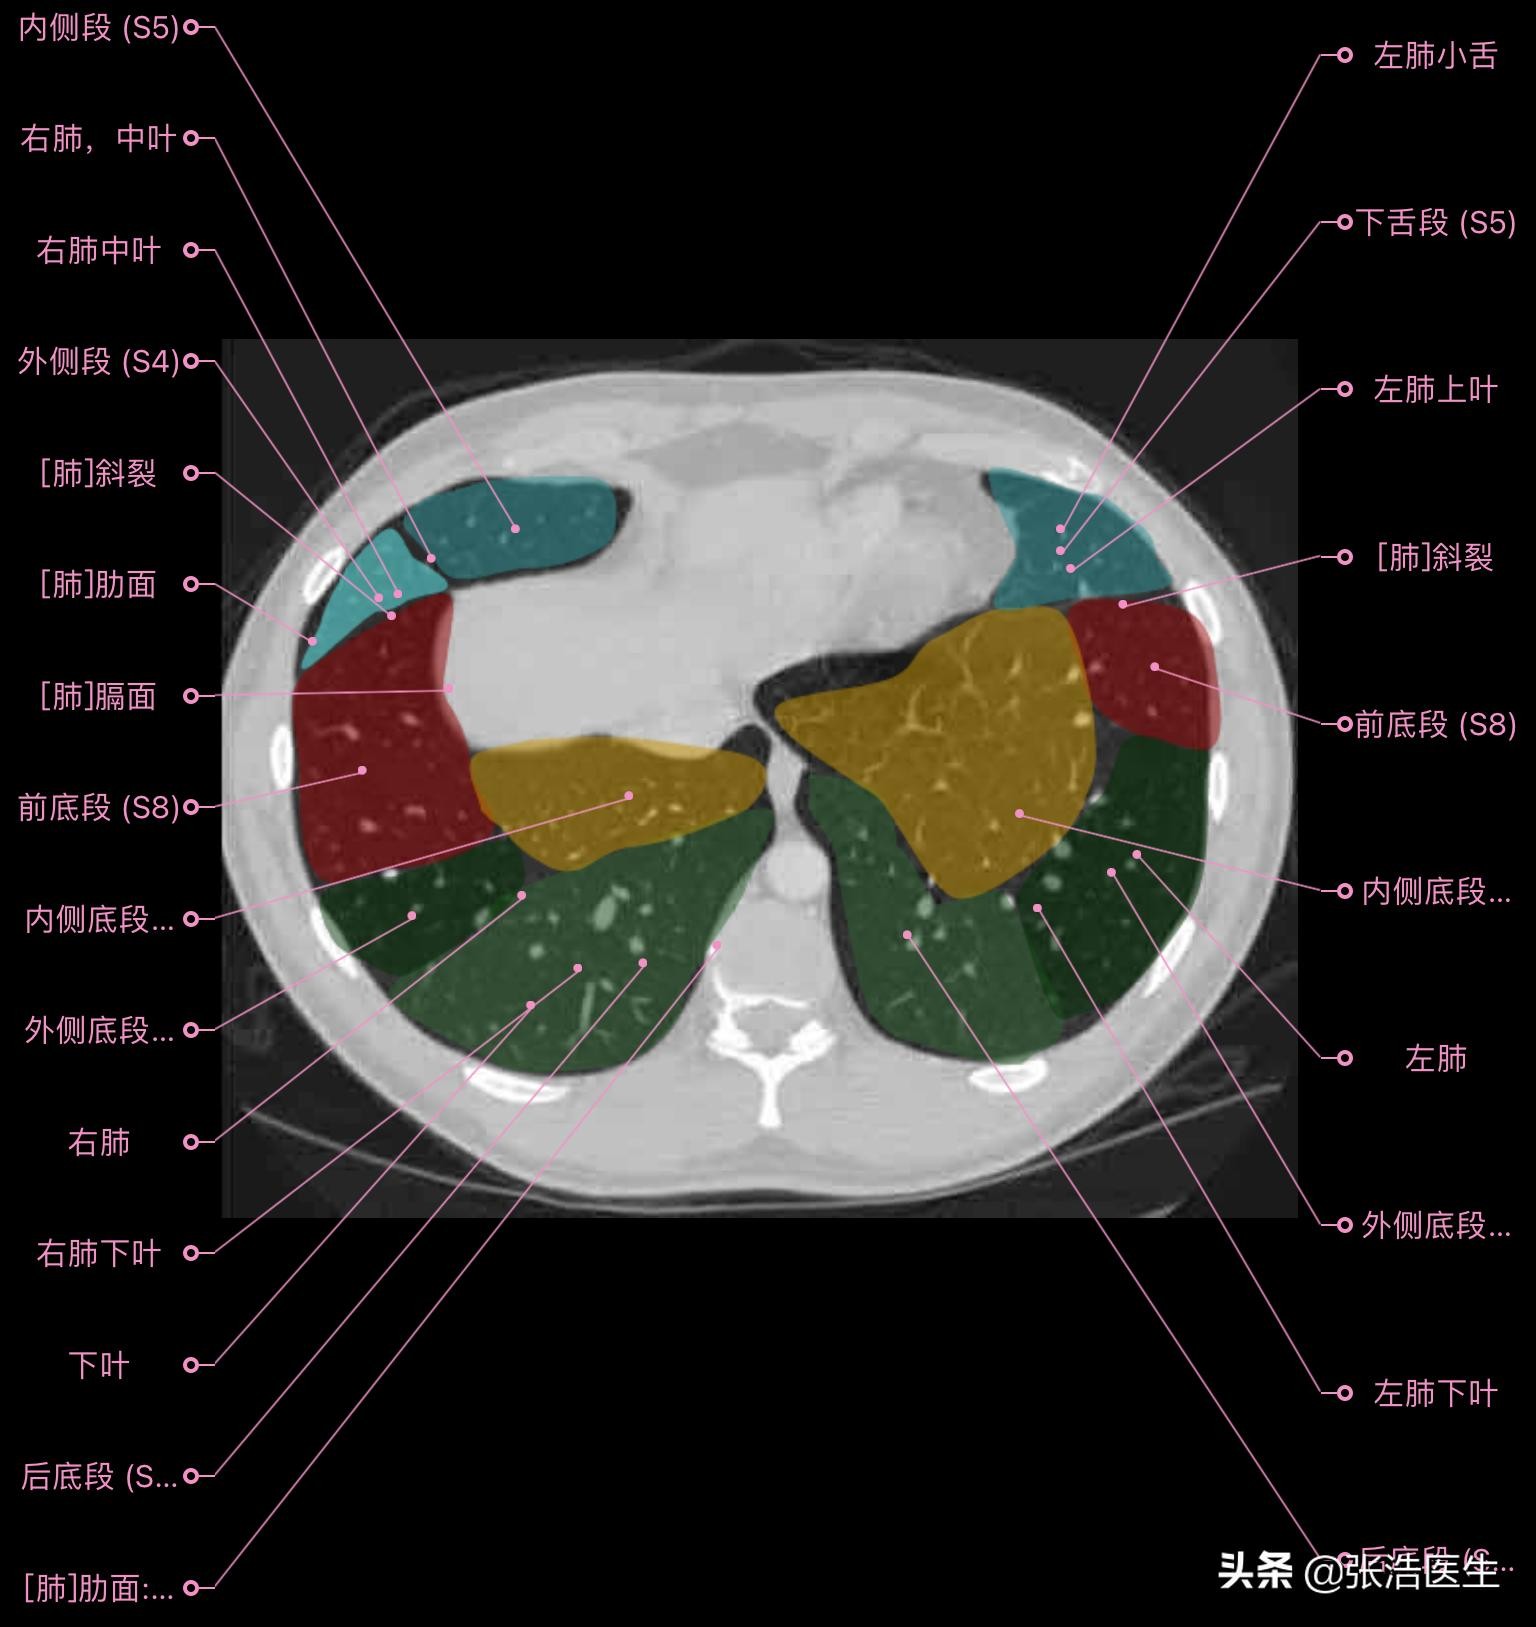

肺部CT横断面高清解剖图谱(图层4)

肺部CT横断面 高清解剖图谱

精选15层常用解剖断面

每一层都带有详细标注,值得收藏学习!